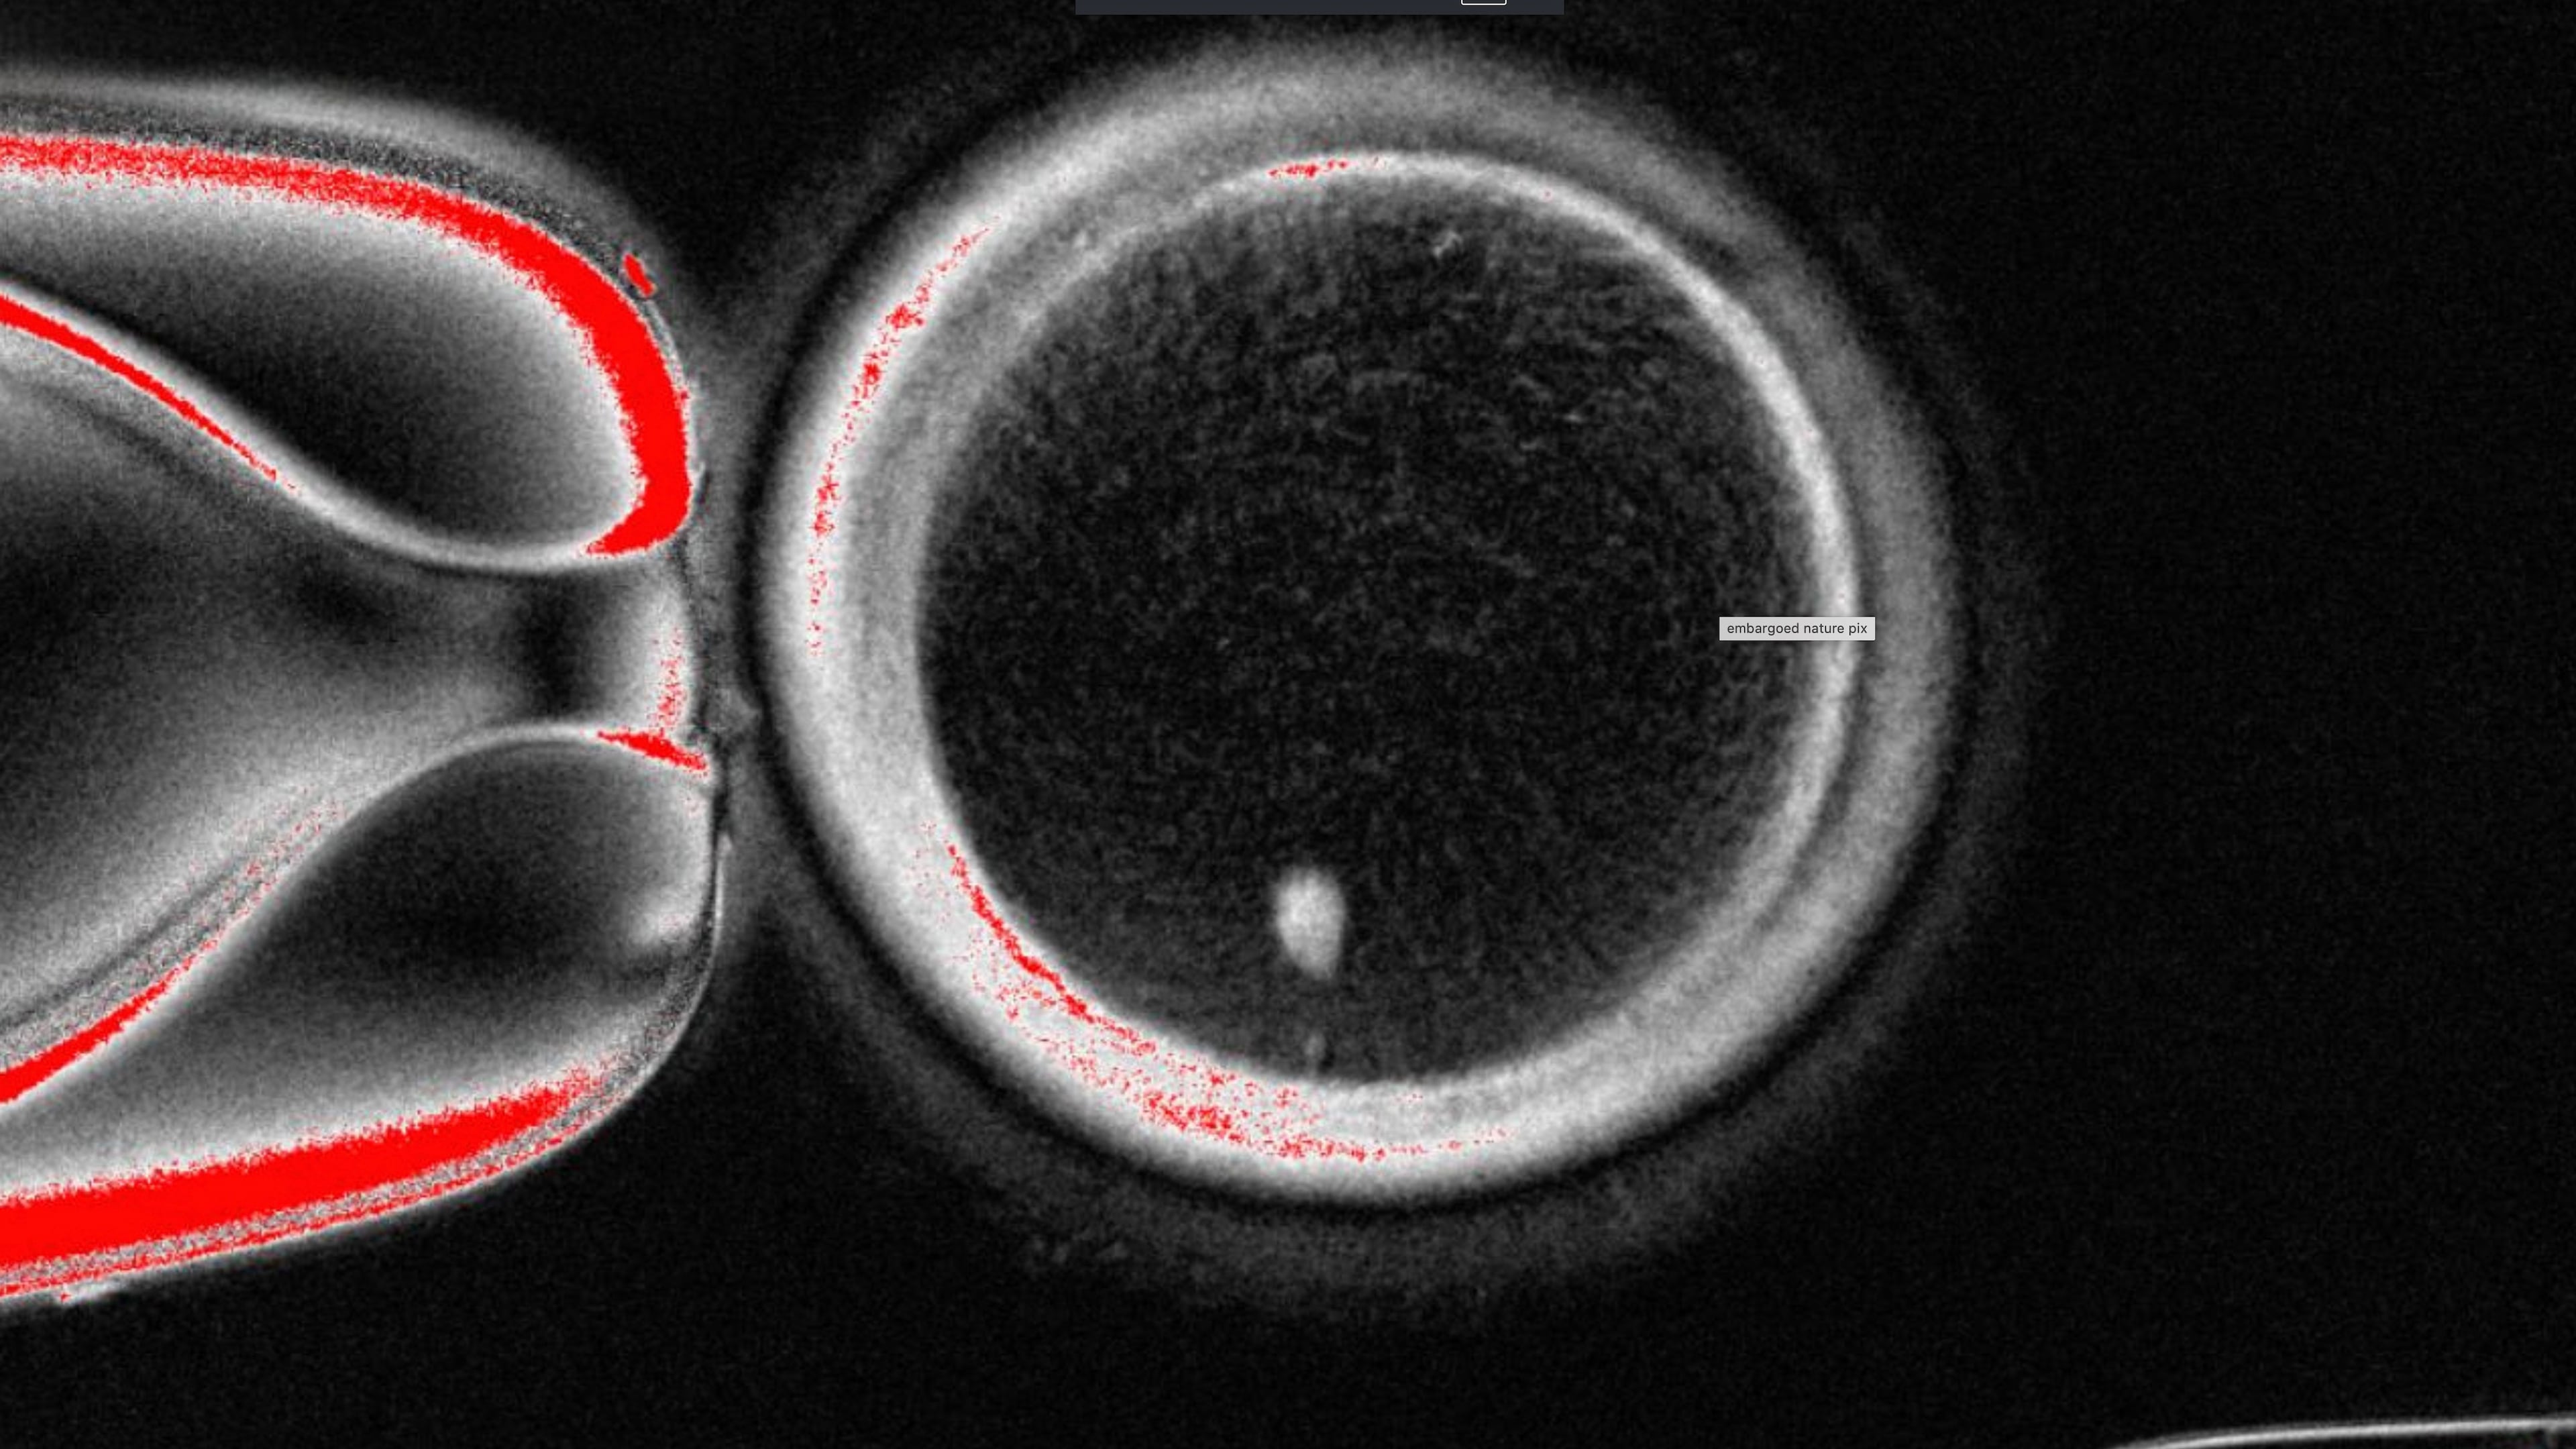

The OHSU team removed the nucleus from a human egg cell and replaced it with the nucleus from a human skin cell. But a skin cell contains two sets of chromosomes, and eggs and sperm are supposed to each contain only one set that combine during fertilization. The researchers therefore induced the egg-like cells to discard extra chromosomes, injected donated sperm and jumpstarted post-fertilization development.

About 9% lasted for six days in lab dishes, reaching the blastocyst stage of early embryo development, before the experiment was stopped.